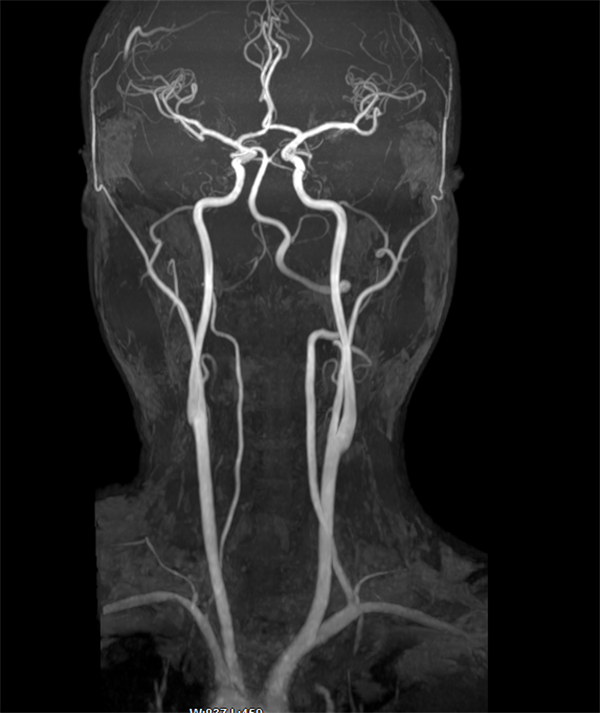

MRA即磁共振动脉血管成像。头颅MRA对颅脑和颈部的大血管显示效果好,可对颅内的血管有无狭窄、有无闭塞、有无血栓及出血性疾病,脑动脉瘤和脑血管畸形进行初步诊断和评估。